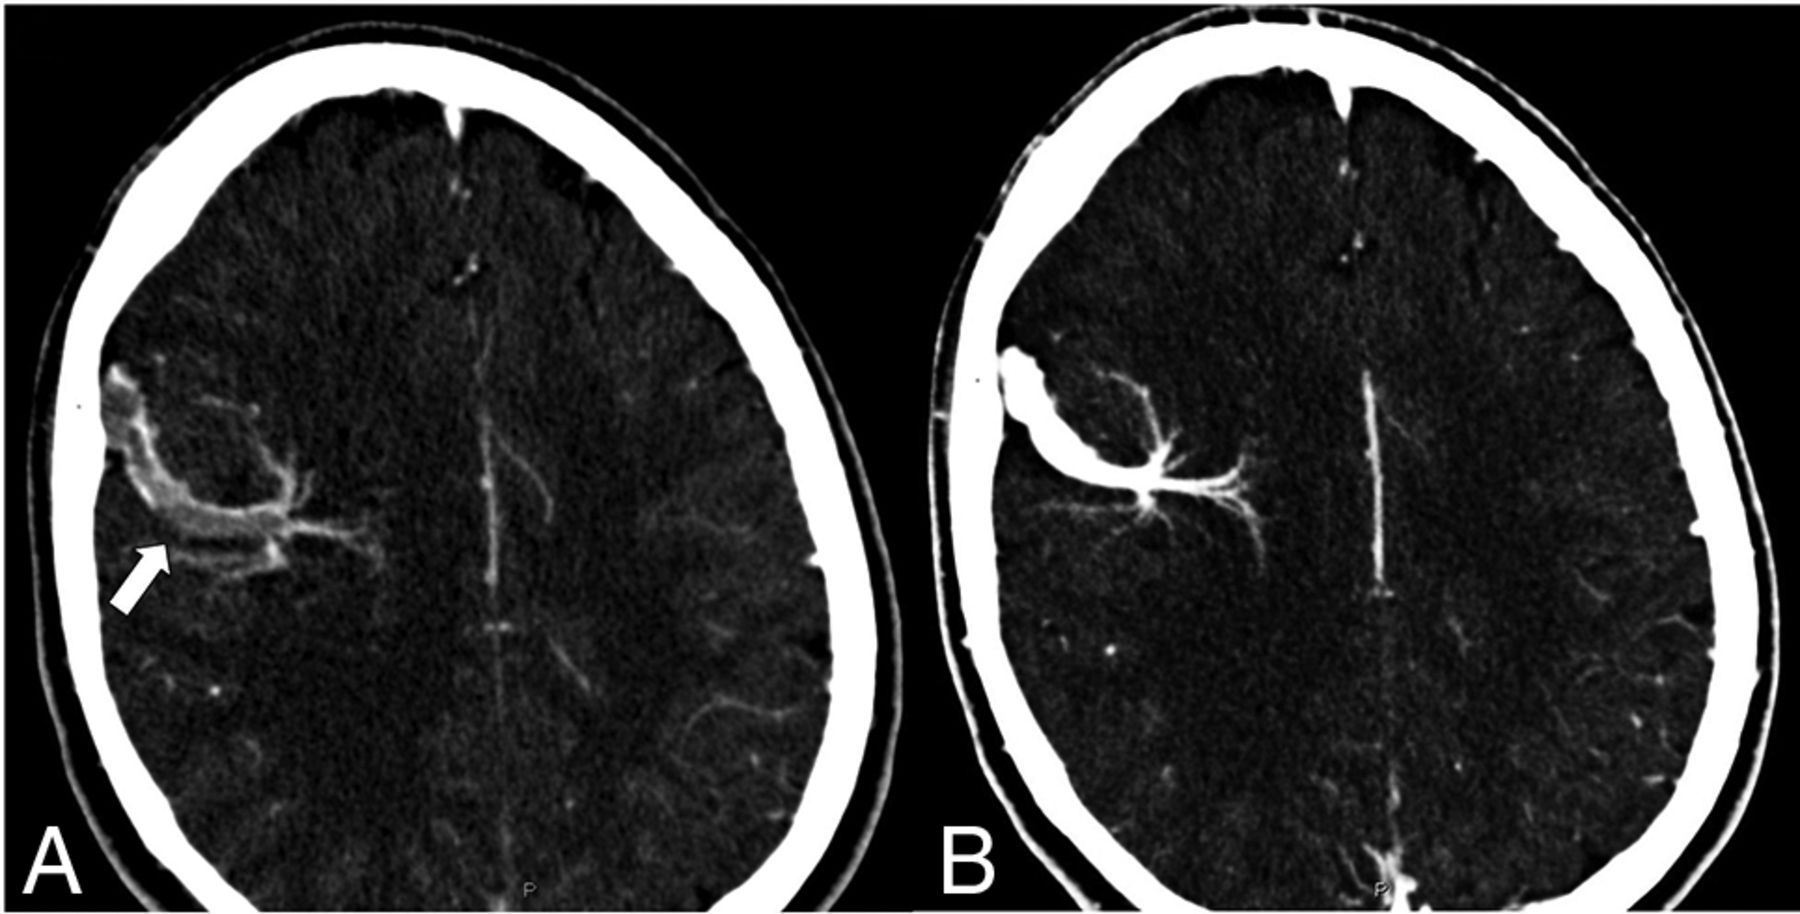

A young patient presented with a sudden onset of severe headaches after a marathon race. Presentation CTV (A) shows thrombosis of a DVA collector vein (arrow) overlying the right frontal cerebral convexity. The patient was placed on antiplatelet medication, and a follow-up CTV (B) showed a resolution of the thrombus.